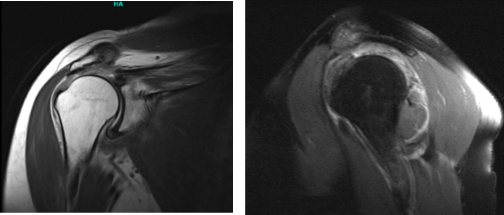

The patient presented an MRI result and showed complete tears of the supraspinatus and infraspinatus tendons with retraction as described. Subscapularis tendinosis with superimposed low-grade intrasubstance partial-thickness tear. Mild supraspinatus and infraspinatus muscle atrophy.

MRI right shoulder non-contrast